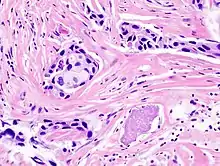

Histopathology: microscopic appearance of invasive ductal carcinoma of the breast. The slide is stained with Haematoxylin & Eosin.

• Histopathology – the microscopic examination of stained tissue sections using histological techniques. The standard stains are haematoxylin and eosin, but many others exist. The use of haematoxylin and eosin-stained slides to provide specific diagnoses based on morphology is considered to be the core skill of anatomic pathology. The science of staining tissues sections is called histochemistry.